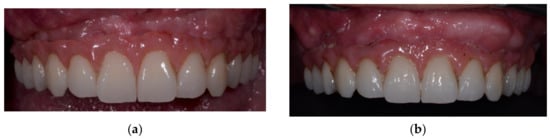

2. Case Report